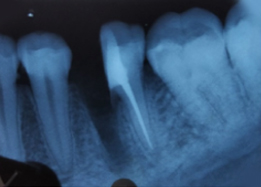

Half of Lower molar tooth along with diseased root removed & rest part is saved.

Pre-OP IOPAR